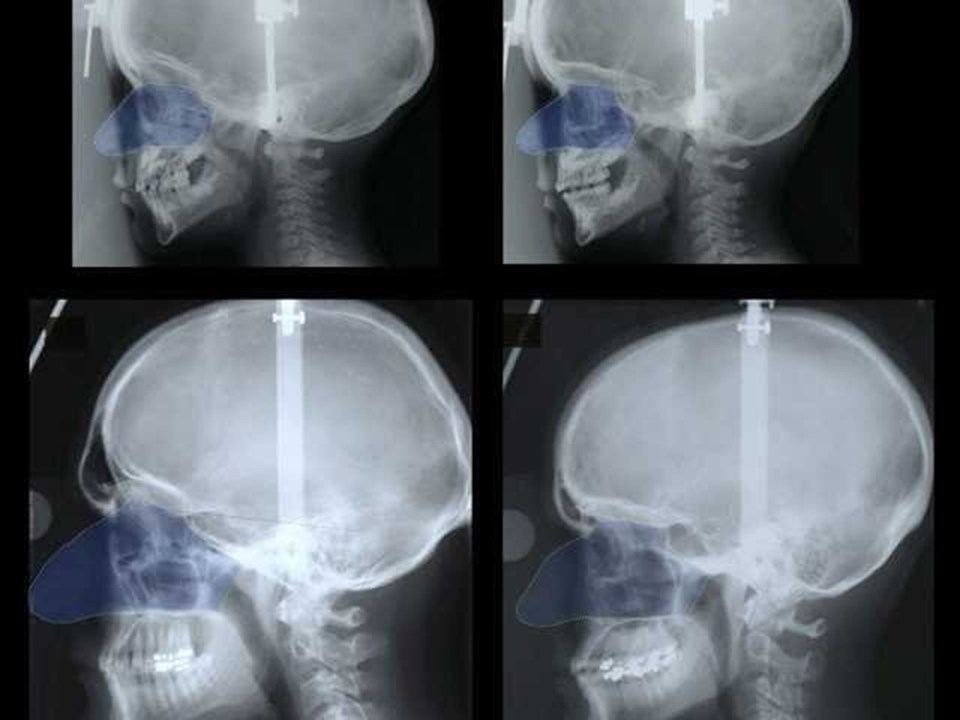

Sol üst ve alt kare, ergenlik öncesi ve sonrası erkek burnunu; sağ üst ve alt kare ise ergenlik öncesi kadın burnunu gösteriyor.

Sol üst ve alt kare, ergenlik öncesi ve sonrası erkek burnunu; sağ üst ve alt kare ise ergenlik öncesi kadın burnunu gösteriyor.